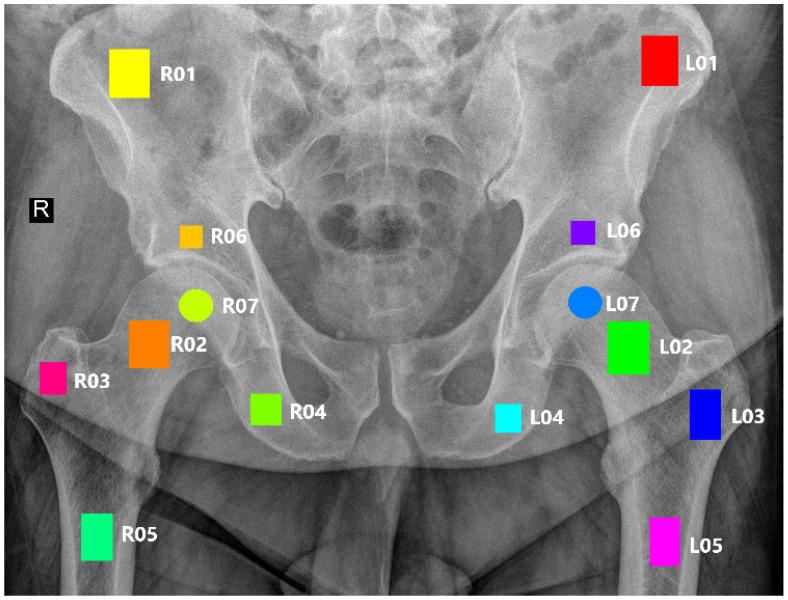

The purpose of this paper is to assess the determination of male and female sex from trabecular bone structures in the pelvic region. The study involved analyzing digital radiographs for 343 patients and identifying fourteen areas of interest based on their medical significance, with seven regions on each side of the body for symmetry. Textural parameters for each region were obtained using various methods, and a thorough investigation of data normalization was conducted. Feature selection approaches were then evaluated to determine a small set of the most representative features, which were input into several classification machine learning models. The findings revealed a sex-dependent correlation in the bone structure observed in X-ray images, with the degree of dependency varying based on the anatomical location. Notably, the femoral neck and ischium regions exhibited distinctive characteristics between sexes. This insight is crucial for medical professionals seeking to estimate sex dependencies from such image data. For these four specific areas, the balanced accuracy exceeded 70%. The results demonstrated symmetry, confirming the genuine dependencies in the trabecular bone structures.

本文的目的是评估从骨盆区域的小梁骨结构确定男性和女性性别的方法。该研究包括分析343名患者的数字射线照片,并根据其医学意义确定14个感兴趣的区域,身体两侧各有7个区域以保持对称。使用各种方法获得每个区域的纹理参数,并对数据归一化进行了深入研究。然后评估特征选择方法以确定一小部分最具代表性的特征,将这些特征输入到几个分类机器学习模型中。研究结果显示,在X射线图像中观察到的骨结构存在性别依赖性相关性,其依赖程度因解剖位置而异。值得注意的是,股骨颈和坐骨区域在两性之间表现出独特的特征。这一见解对于试图从此类图像数据中估计性别依赖性的医学专业人员至关重要。对于这四个特定区域,平衡准确率超过70%。结果显示出对称性,证实了小梁骨结构中存在真正的依赖性。